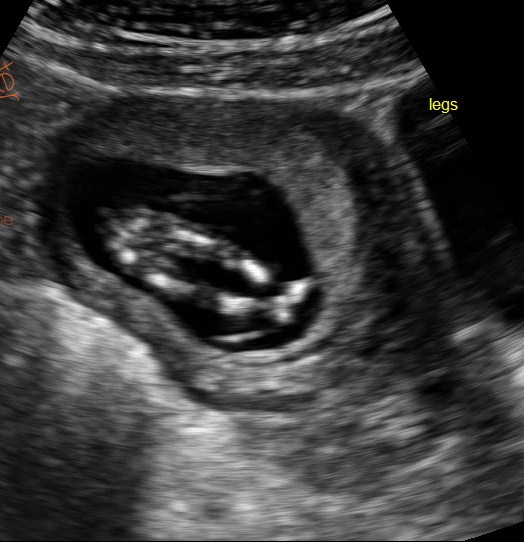

The first two pics are profile and nub shots. Let me know if you are unable to see them. It is 12 weeks and 4 days actually.

ahh sorry for some reason I couldnt see the other pics earlier. The nub may be just about visible in the first pic but it looks pretty blurry, I would stab a guess at boy but not 100%. Have you tried asking on any other sites? xx

Very maybe girly....